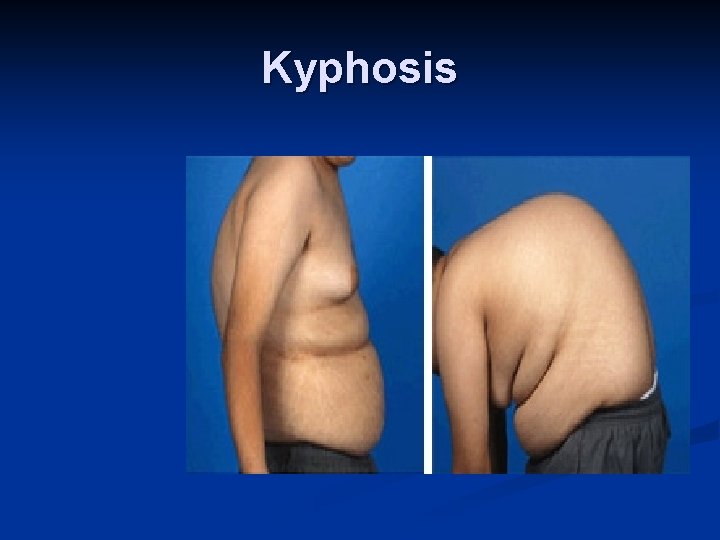

Manifestations of Osteomalacia Localized bone pain Difficulty walking Low back pain Fractures are common, and delayed healing occurs Muscular weakness Weight loss Progressive deformities of the spine (kyphosis)

Kyphosis